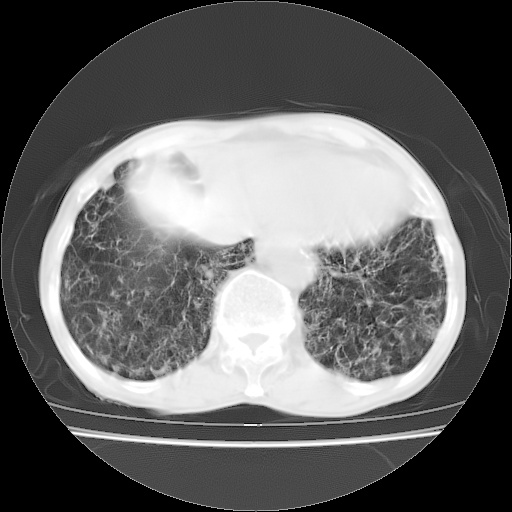

病人发热、气促就诊。原二周前已行ct扫描,当时诊断为双肺下叶、右肺中叶支气管扩张并感染,双肺上叶片状渗出性病变。今天复查胸部ct,双肺下叶支气管扩张并感染病灶较前明显吸收,但双肺上叶渗出性病变较范围较前明显增大。

双肺多发大片状、斑片状高密度渗出影,部分实变,考虑病毒性肺炎。